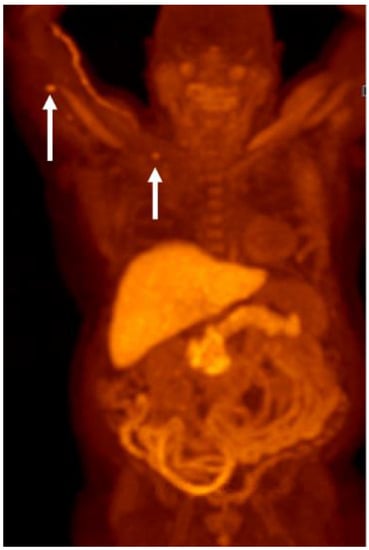

Detection of Loco-Regional Disease and Distant Metastases